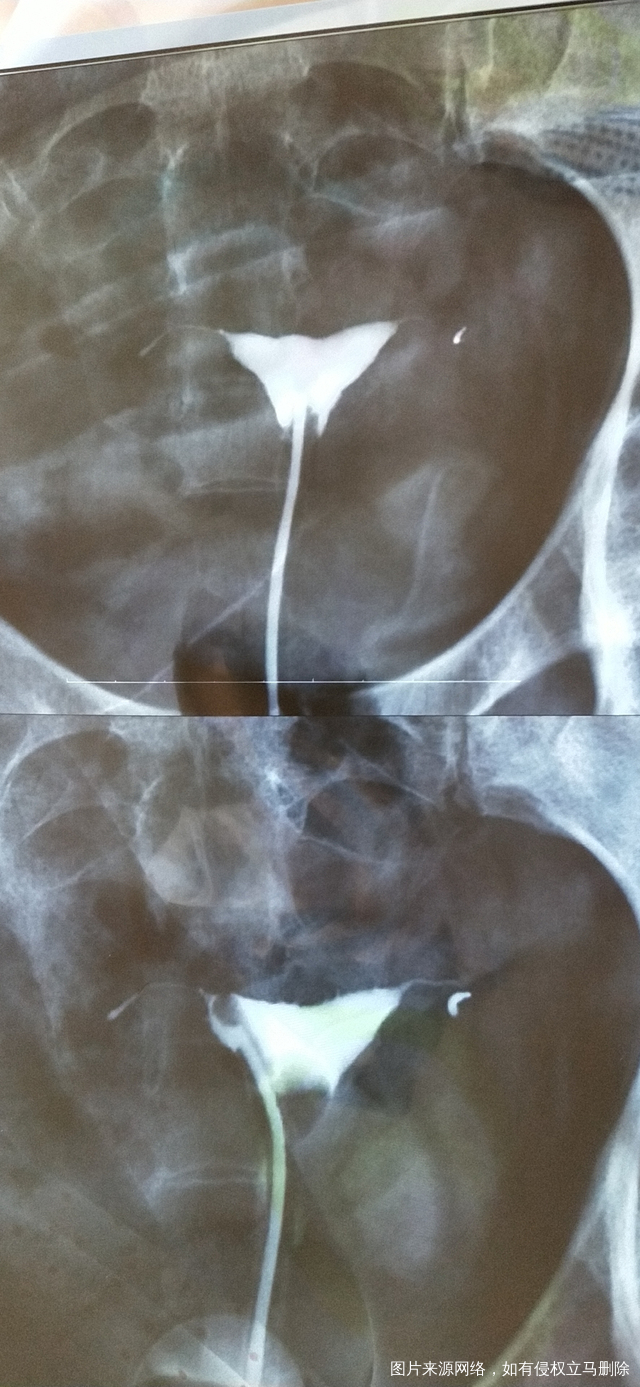

做完输卵管造影第六天了小腹还是感觉沉甸甸的如

可以热敷腹部,如果有发热,腹痛加剧,白带量多,有异味,随时就医